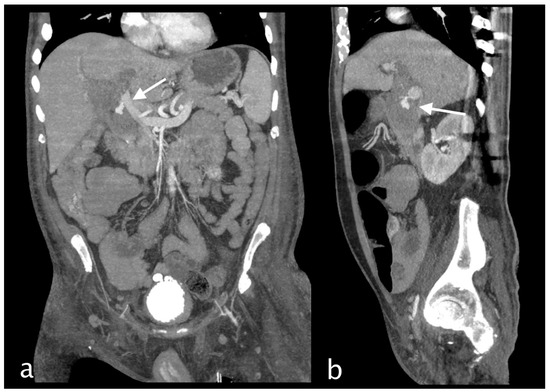

2. Imaging

3.1.3. Imaging and Diagnostic Findings